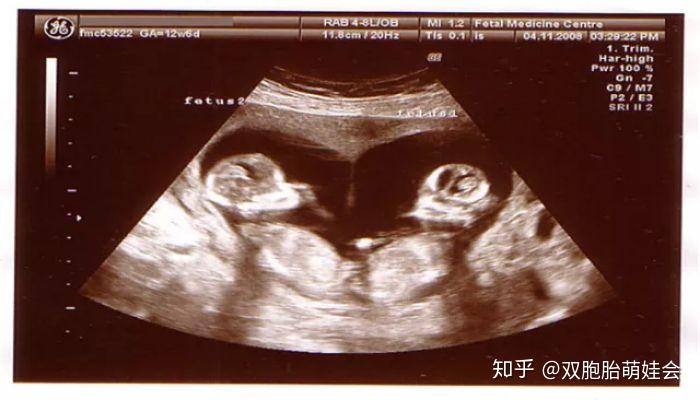

双卵双胞胎是不是龙凤胎几率很大,这个是今天的b超图怀孕50来天!

怀孕啦!双胞胎妈妈的孕早期分享

连载(四)|圆圈妈双胞胎怀孕过程第7周